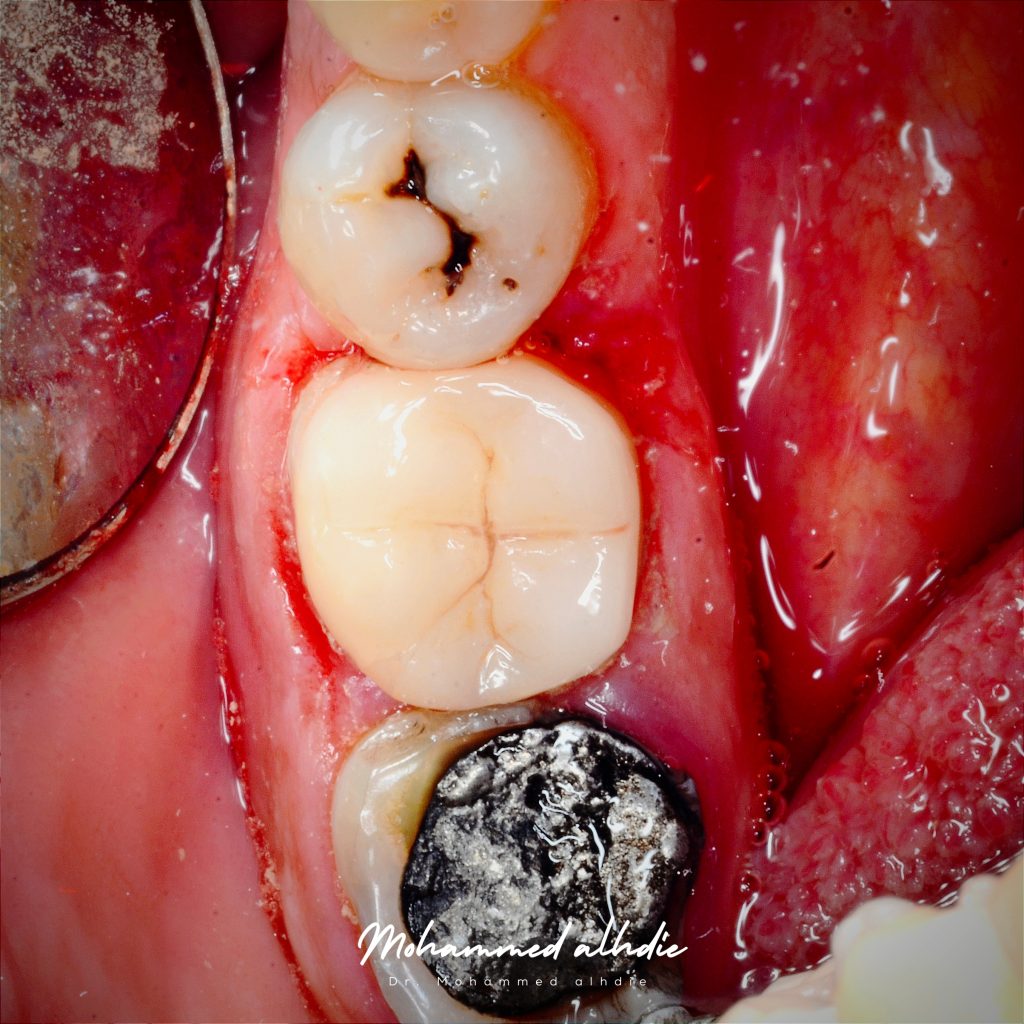

الصورة رقم 3: الوصول إلى التجويف بعد فتح 3 قنوات ونبحث عن القناة الأخيرة بشكل واضح

الصورة رقم 4: عندما اعتقدت أن القناة الأخيرة متكلسة أيضًا، قمت بعمل ثقب، ولكن في البداية اعتقدت أن القناة مفتوحة